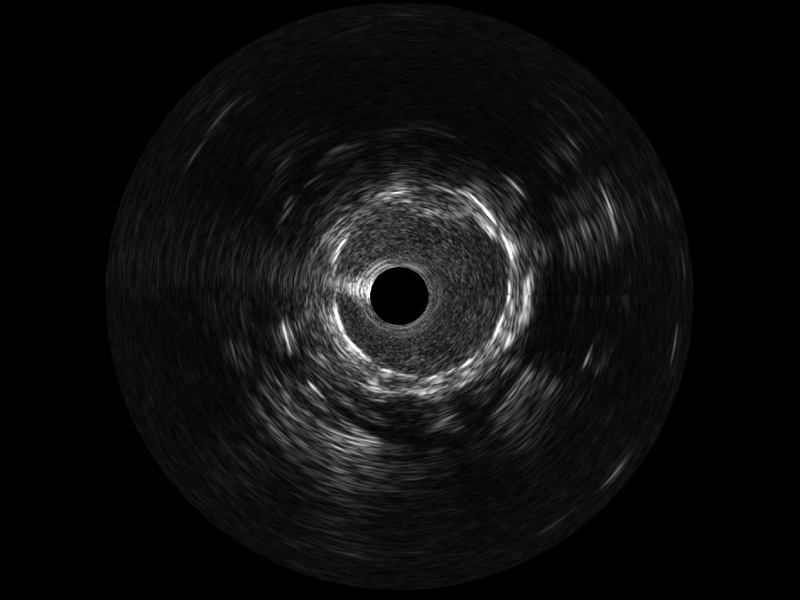

• 传统IVUS图像

对比传统IVUS导管成像,美狮贵宾会官网宽频IVUS图像的近场支架梁显影更细腻,远场中膜外血管仍清晰可辨,兼顾远中近,兼顾分辨力与穿透深度